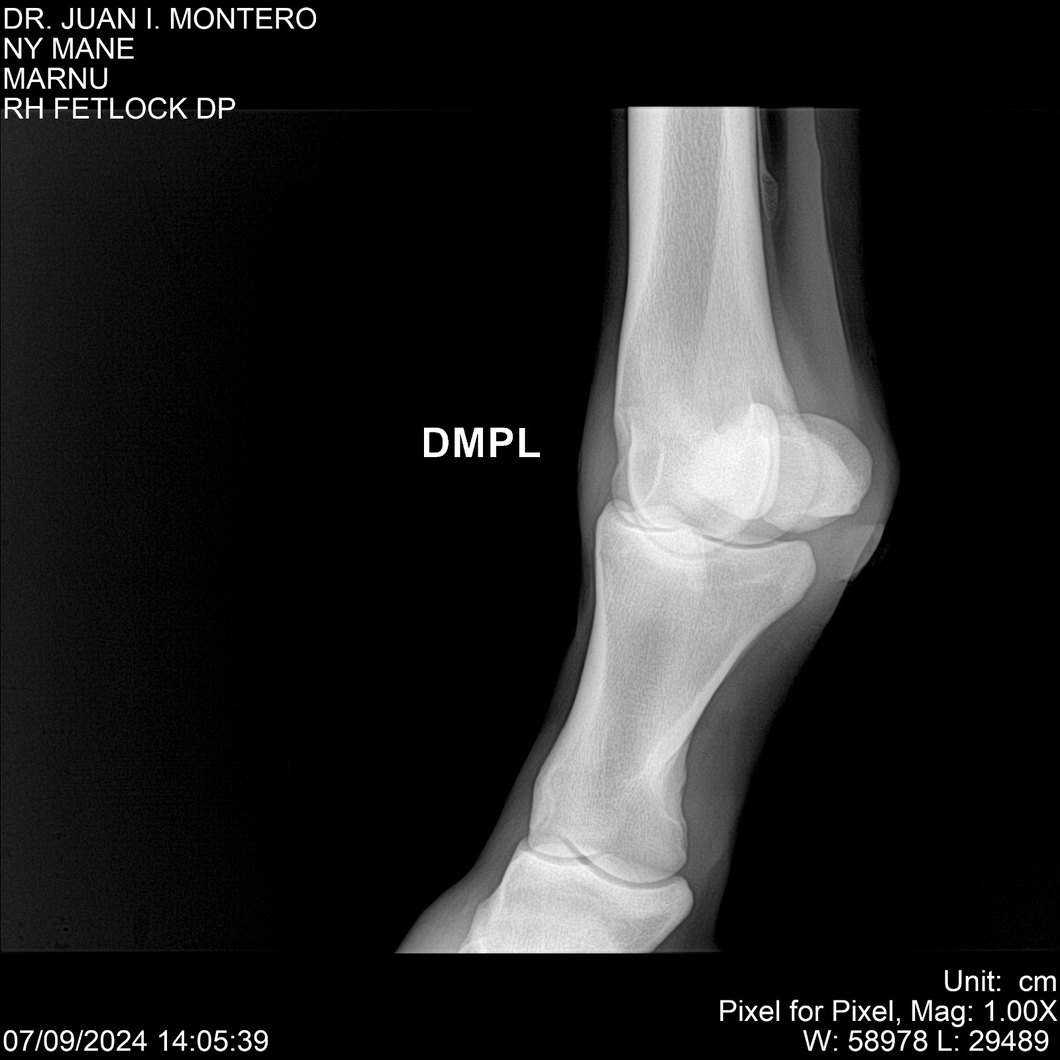

LOTE 20, NY MANE Lote Anterior Volver al remate Lote Siguiente Ficha Contacto Montevideo - Ficha del Lote Identificador: #282520 Categoría: Yeguarizos 76 Visualizaciones ClicData Contacto Empresa: Abelenda N. R., Walter Hugo Nombre*: Teléfono* : E-mail* : Mensaje Enviar Registrese gratis Este contenido Exclusivo está disponible sólo para usuarios registrados Ingresar